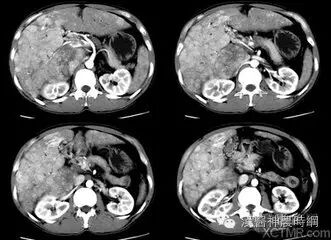

2.计算机X线体层扫描(CT)  CT是一种安全、无创伤、高分辨力的检查方法。对肝癌的定位诊断很有价值。CT能显示肿瘤的大小、位置、数目及与周围脏器和大血管的关系,可检出1cm左右的早期肝癌。并有助于了解是否伴发肝外转移,如肝门淋巴结,胰头后淋巴结等。结合增强扫描可以判断病变的性质,对肝癌与肝血管瘤的鉴别有较大的价值。平扫下肝癌多为低密度占位,边缘清晰或模糊,部分有包膜的肝癌可显示晕圈征。较大的肝癌可见更低密度的坏死区,少数肝癌可见钙化。增强扫描有滴注法、大剂量推注、推注加动态扫描等。肝癌在动脉期尤以注药20s内强化最为明显,癌灶密度高于周围肝组织。30~40s后造影剂进入细胞间隙转入实质期,病灶又恢复为低密度,显示更为清晰。近将肝动脉造影与CT检查相结合,开展CT动脉造影(CTA)和CT动脉门脉造影(CTAP),对提高小肝癌的检出率有一定价值。也有人在CT检查前一周经肝动脉插管注入碘化油(lipiodo1),再做CT扫描,这种lipiodol-CT可检出0.5cm的小肝癌。对于<1cm的肝癌,Uchida报告US、CT、肝动脉造影和几种CT检查的分辨力为:US 63%、普通CT 12%、滴注法增强扫描65%、CTA 71%、CTAP 80%、lipiodol-CT 89%。